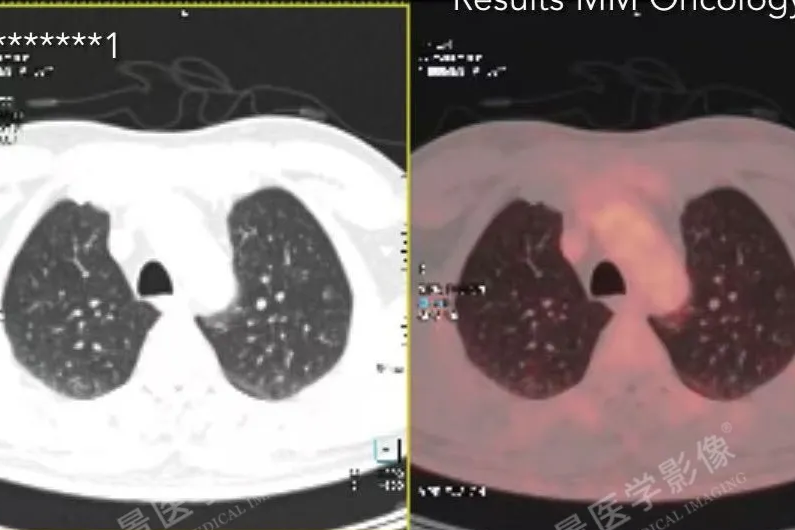

「牵一发而动全身」—以为是肺的事,PET/CT 揭秘—全身淋巴瘤